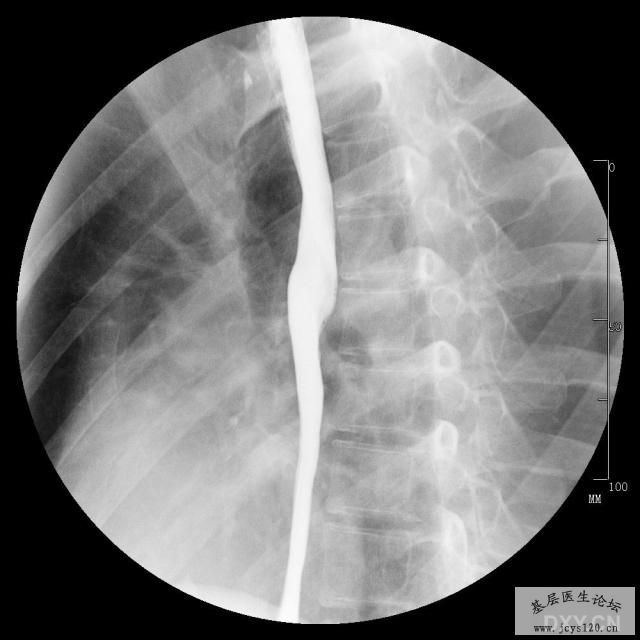

女,22岁,时有恶心,不吐,有吞咽困难感。 阅读全文>